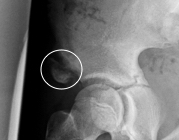

Abb. 1: Komplette Avulsion der Sehne des rechten M. adductor longus vom Os pubis mit deutlicher Retraktion um mehrere Zentimeter (der weiße Kreis umfasst Symphyse, Defektzone und die retrahierte Sehne). Nach konsequenter konservativer Therapie mit abgestuftem Rehabilitationsprogramm und schrittweisem Belastungsaufbau über einen Zeitraum von zwölf Wochen konnte der Profi-Fußballer beschwerdefrei auf sein bisheriges Spitzenniveau zurückkehren. Die Bildgebung zeigte im Verlauf eine narbige Überbrückung des Defektes, klinisch war der M. adductor longus ohne funktionelle Defizite.